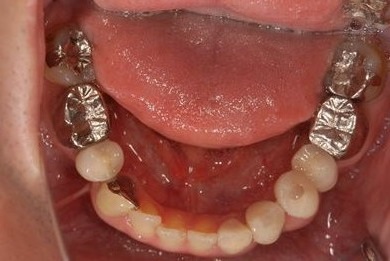

インプラントの症例写真 IMPLANT

骨再生インプラント治療

| 性別/年齢 | 男性 / 34歳 | ||||||||||||||||||||||||||||||||

| 治療方針 | ソケットリフトにて上顎洞を拳上し、インプラント治療を可能にする。 | ||||||||||||||||||||||||||||||||

| 治療内容 | インプラント1本(ソケットリフト)、メタルボンドセラミッククラウン1本 | ||||||||||||||||||||||||||||||||

| 総治療費 | 547,838円 | ||||||||||||||||||||||||||||||||

| 治療期間 | 4ヶ月 |